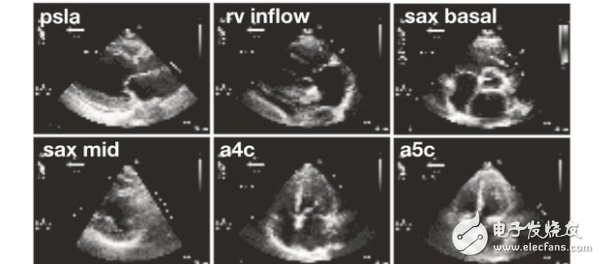

7037 這個星球上的人們,或許還沒有做好迎接人工智能醫(yī)生的準(zhǔn)備。不過,加州大學(xué)舊金山分校(UCSF) 的研究人員培育的AI,已經(jīng)在心臟圖像的分類比賽上,超過了參賽的人類心血管醫(yī)師。